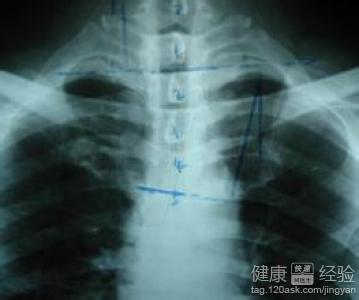

1心肌炎是一種由於患者受到了感染,化學等因素而引起的心肌性的炎症疾病,該病可以使患者的心肌受到了損害,常先有原發感染的表現,如病毒性者常有發熱、咽痛、咳嗽、嘔吐、腹瀉、肌肉酸痛等。

2而心肌病主要是可以分為原發性和繼發性的兩種疾病,通常按照不同患者的病症情況,可以分為三型:擴張型心肌病,肥厚型心肌病,限制型心肌病。該病通常可以引起患者的心髒出現了擴大的情況,最終發展成為了心力衰竭的一種心髒病.

3此外心肌病的發病年齡通常在中老年人群中,具有一定的家族遺傳的特點。而心肌炎的疾病則是以為兒童和青年人群為主,重者可發生猝死。建議患者一旦出現了持續性的不適時,應盡快到正規醫療機構進行治療。